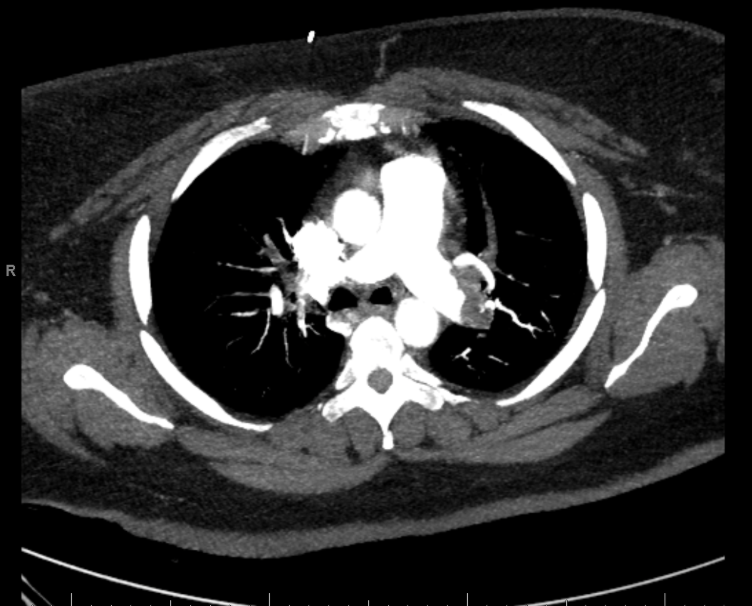

Case Presentation: Cardiopulmonary resuscitation (CPR) is a critical intervention in cardiac arrest management, essential for maintaining circulation and oxygenation to avert irreversible brain damage. This case report highlights the impact of high-quality CPR on neurological outcomes, even after extended resuscitation.A 45-year-old sedentary female with multiple sclerosis (MS) and morbid obesity with a BMI of 53 presented with gastrointestinal and dyspnea symptoms post-immunotherapy. Imaging identified bilateral lower lobe pulmonary embolisms and a saddle embolus with significant thrombus burden and right heart strain. During suction thrombectomy, the patient experienced pulseless electrical activity (PEA) arrest. Manual CPR was immediately initiated, and the patient was intubated 12 minutes later. Due to the patient’s body habitus, robotic compressions could not be performed. Sustained return of spontaneous circulation (ROSC) was achieved after 70 minutes, despite transient ROSC episodes. Throughout the resuscitation, she received 13 doses of epinephrine and 4 doses of sodium bicarbonate. Following the event, the patient required hemodialysis due to renal deterioration but stabilized hemodynamically five days later. She regained cognitive capacity and full motor function within 10 days, leading to discharge after a 28-day hospitalization.